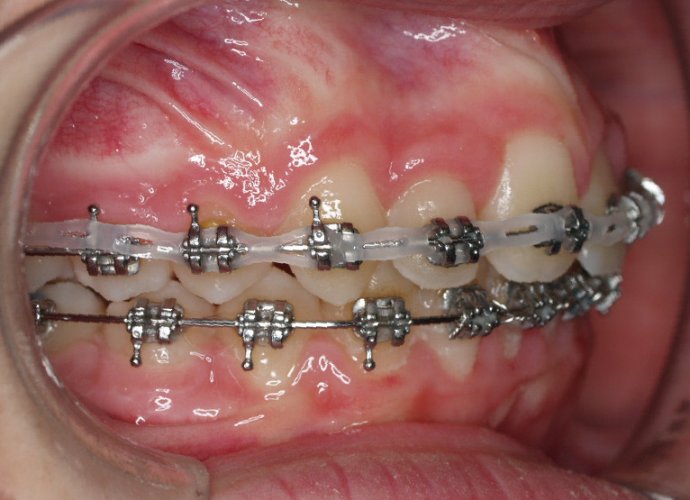

- Realizar un tratamiento ortodóncico para mover los dientes y cerrar el diastema.

Si su frenillo labial es demasiado grande, puede que le remitan a un especialista para someterse a un procedimiento quirúrgico llamado frenectomía. Este procedimiento consiste en cortar el frenillo y volverlo a colocar para permitir que tenga más flexibilidad. Cuando la frenectomía se realiza en un niño, el espacio puede llegar a cerrarse por sí solo. Si se trata de un adolescente o un adulto, puede que sea necesario cerrarlo con ortodoncia. Es esencial acudir al dentista para saber cuál de estas opciones es la adecuada en su caso.